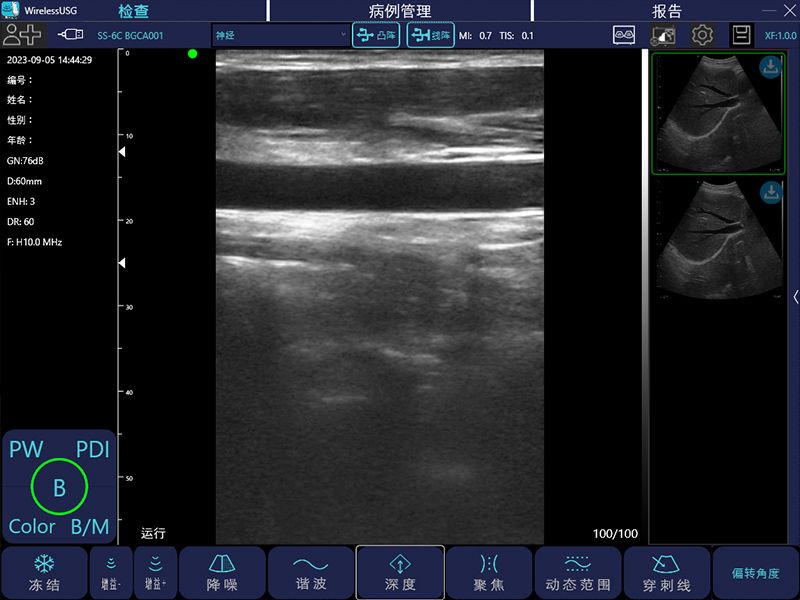

- 成像模式: B、B/M、Color、PW、PDI

- 探头类型:凸阵、线阵、相控阵、微凸、腔内、直肠

线阵:7.5MHz/10MHz,20/40/60/100mm,40mm

- 图像调节:黑白图像增益、分段增益TGC、动态范围、焦点、深度、反相脉冲谐波、降噪、彩色增益、血流采样框大小、PRF